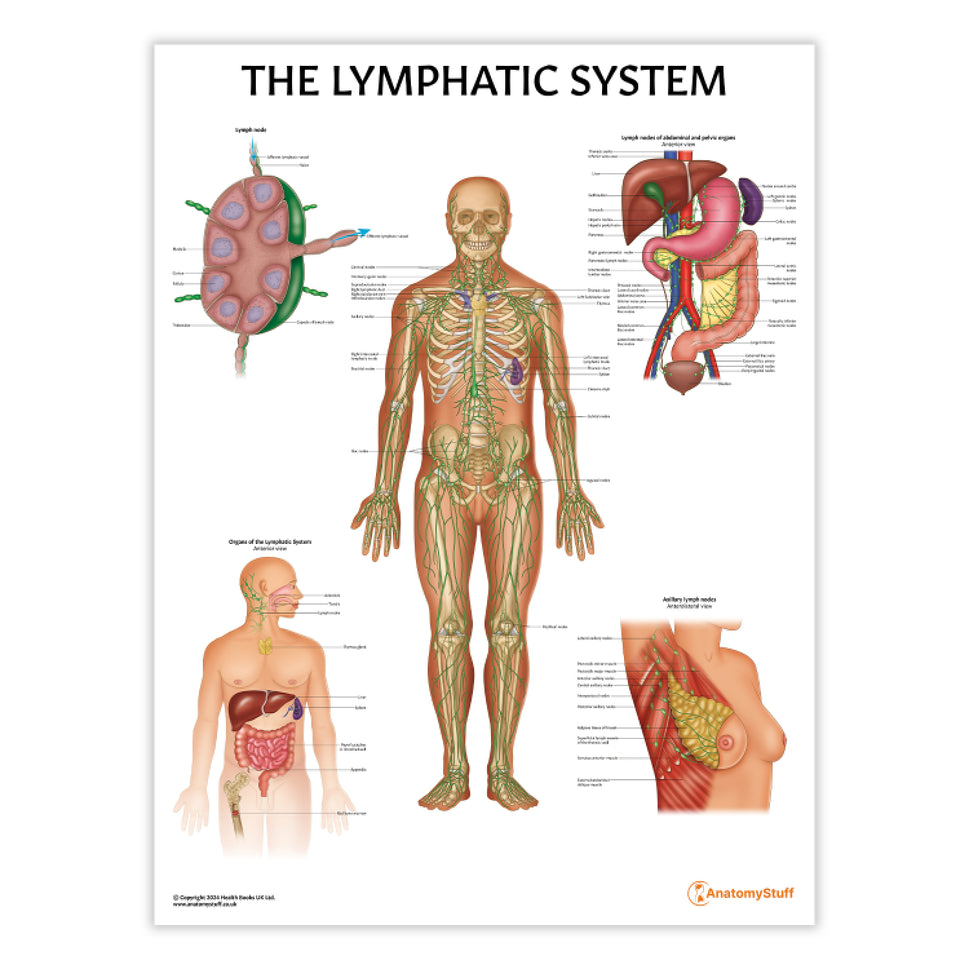

Enhance medical education with our collection of digestive system anatomical models including the stomach, liver, gallbladder, pancreas & colon models. Discover the anatomy of healthy organs as well as common gastrointestinal diseases such as stomach ulcers, gallstones and liver cirrhosis. Our digestive system anatomy posters are ideal for study and patient education.

At AnatomyStuff we stock a diverse range of digestive system anatomical models to suit your training needs. From budget models and affordable medical education posters to highly advanced 3D printed bowel models, you can transform medical training and patient education. As well as our own exclusive collection, we are proud resellers of 3B Scientific, Anatomy Lab, Denoyer-Geppert Science Company, ESP Models, Erler Zimmer and GPI Anatomicals. Explore our exclusive collection of digestive system anatomy charts, posters, fine art prints and digital anatomy study guides. Discover the anatomy of key organs like the liver, stomach, pancreas and bowel as well as the pathophysiology of common conditions like peptic ulcer disease, coeliac disease, IBD and much more. We have anatomy posters suitable for school children all the way up to medical degree level. From a liver anatomy poster to a digital study guide all about common GI disorders, find exactly what you need right here to enhance medical training and patient education.